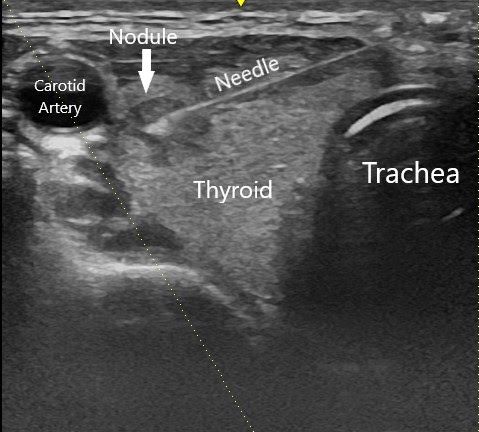

Often an ultrasound probe is used to determine the location of the mass and to guide the needle safely into the mass while avoiding the nearby blood vessels (the needle shows up on the ultrasound in real-time!). Using ultrasound is particularly important when the mass cannot be felt easily. Use of ultrasound increases safety as well as accuracy[i].